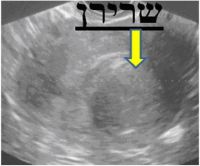

בדיקת האולטרה-סאונד היא בדיקה זמינה ופשוטה. הבדיקה מאפשרת לקבל פרטים על מבנה וגודל הרחם, מיקום וגודל השרירנים, רירית הרחם, אספקת הדם, מראה השחלות, ועוד. אם וכאשר מודגמים שרירנים על מסך הסריקה, מקובל לתעד זאת ולמדוד את גודלם. התמונות מודפסות ישירות ממסך המכשיר. ניתן לראות בהן צללים המייצגים שרירנים, וסמני מחשב המגדירים את מידותיהם.

מיומה2א.JPG מיומה2ב.JPG מיומה2ג.JPG

תרשים מספר 2: תמונות מבדיקות אולטרה-סאונד המדגימות שרירני רחם

במרבית המקרים, לא ניתן לקבל החלטות טיפוליות על סמך תמונות האולטרה-סאונד בלבד. יש לבצע תיעוד נלווה של הממצא במילים ובאיור, המתאר את מספר השרירנים וגודלם ואת מיקומם ביחס לדופן הרחם, ולסכם את תוצאות הבדיקה בצורה מדויקת. הסיכום, הנעשה על ידי הרופא המבצע, משמש לקבלת ההחלטה אודות הטיפול המתאים ביותר לצורך ולרצון האשה.